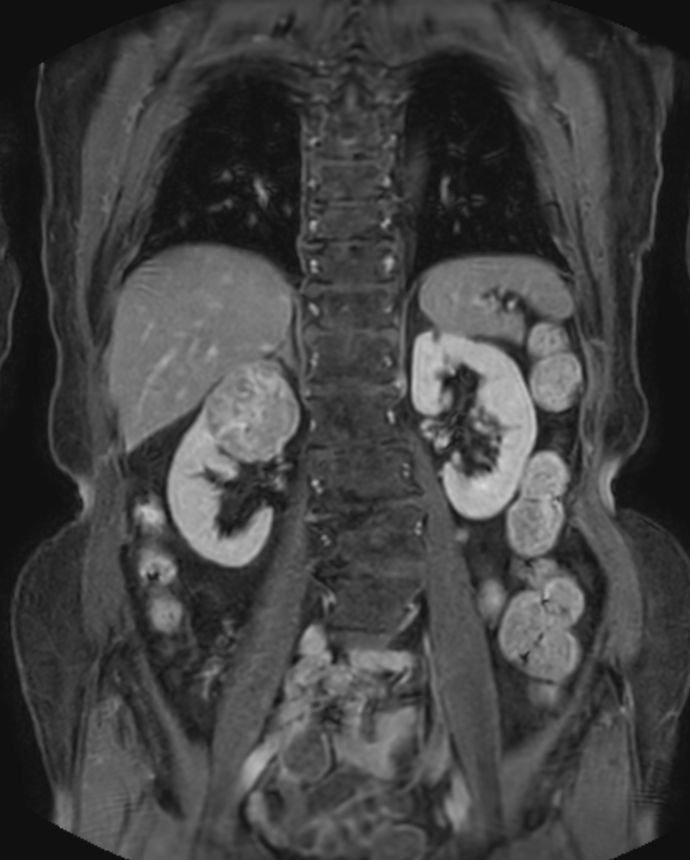

Patient with renal failure. ExamCard includes MultiVane XD to acquire motion-free diagnostic images and 4D FreeBreathing to perform multi-phase contrast-enhanced MRI studies.

4D Free Breathing

4D Free Breathing (subtraction)

4D Free Breathing (MIP)